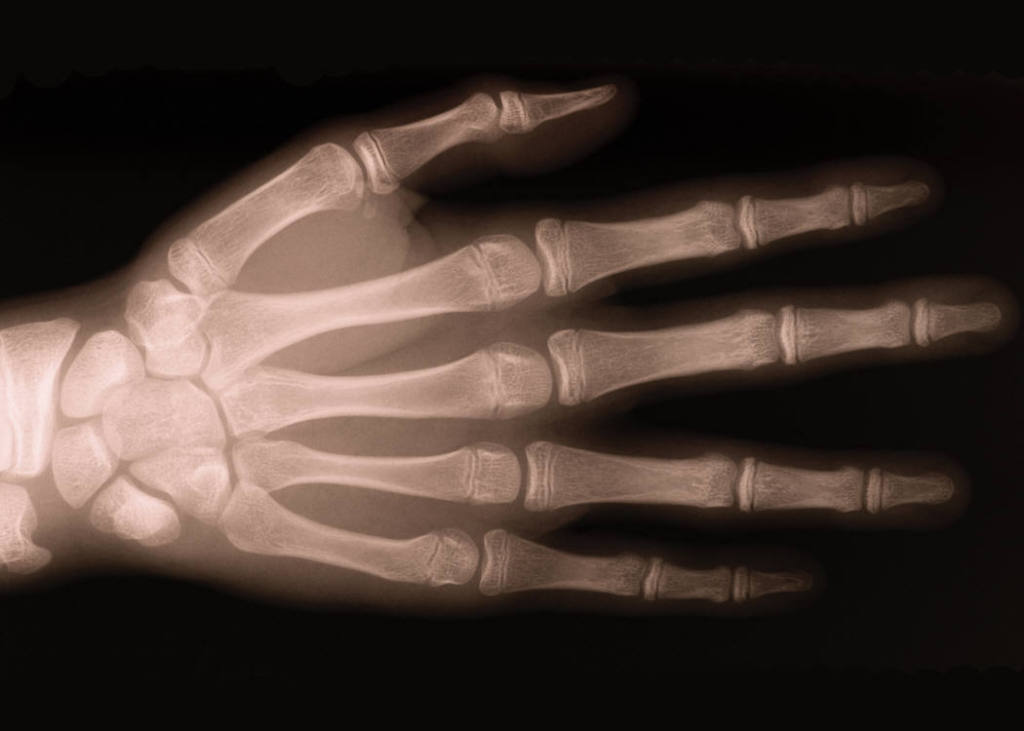

Our office medical assistants are skilled at drawing blood from patients of all ages.  We have an on-site office lab with rapid turnaround and accurate assessment of organ function studies and serologies (disease specific antibodies).  We prefer to review all X-rays and other relavent imaging ourselves and thus can recognize specific features of various disease states allowing more accurate diagnosis and prognosis.